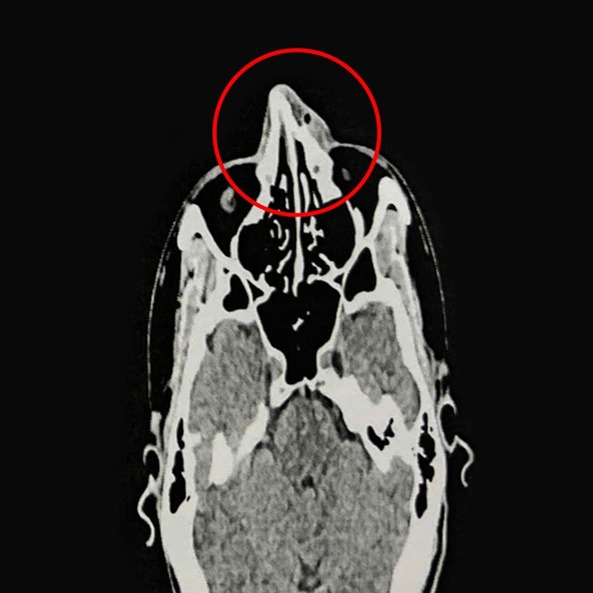

Mới đây, một người đàn ông 35 tuổi ở TP.HCM đã không may bị vợt của đồng đội đánh trúng giữa mũi gây chảy máu, sưng nề. Theo chia sẻ từ ThS.BS.CKI Nguyễn Trung Nguyên, Trung tâm Tai Mũi Họng, Bệnh viện Đa khoa Tâm Anh TP.HCM, cho biết kết quả nội soi và chụp CT 128 lát cắt ghi nhận xương mũi của người đàn ông bị gãy ở vị trí tháp mũi, phù nề tụ khí mô mềm vùng mũi, lệch vách ngăn mũi, viêm mũi xuất tiết. Đây là loại gãy xương mặt phổ biến nhất do mũi ở vị trí trung tâm mặt và nhô ra trước. Người đàn ông được chỉ định phẫu thuật nâng xương mũi, chỉnh hình vách ngăn mũi.

Theo tìm hiểu, bệnh nhân sẽ được điều trị nội khoa 3 ngày giảm phù nề nhằm giúp mũi hết sưng viêm trước khi nhập viện phẫu thuật. Người bệnh được gây mê toàn thân. Qua nội soi kết hợp CT, bác sĩ tiến hành chỉnh hình vách ngăn mũi, rạch niêm mạc vách ngăn phải bị vẹo, tách phần sụn tứ giác và phần xương vách ngăn bị vẹo, cắt bỏ phần xương, sụn vẹo. Sau đó nâng xương chính mũi và ngành lên xương hàm hai bên, chỉnh xương mũi thẳng, cân đối. Cuối cùng, bác sĩ đặt gạc meche chặt vào hốc mũi qua cửa mũi trước, cố định xương mũi đã nâng.